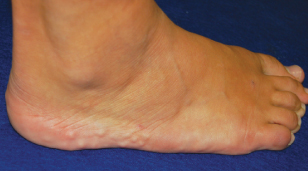

piezogenic papules

<P class=p1><IMG style="MARGIN: 5px; FLOAT: left" src="/sites/default/files/transfer/Screen_shot_2012-03-09_at_3.26.49_PM_thumb.png" width=90 height=90><BR>A...